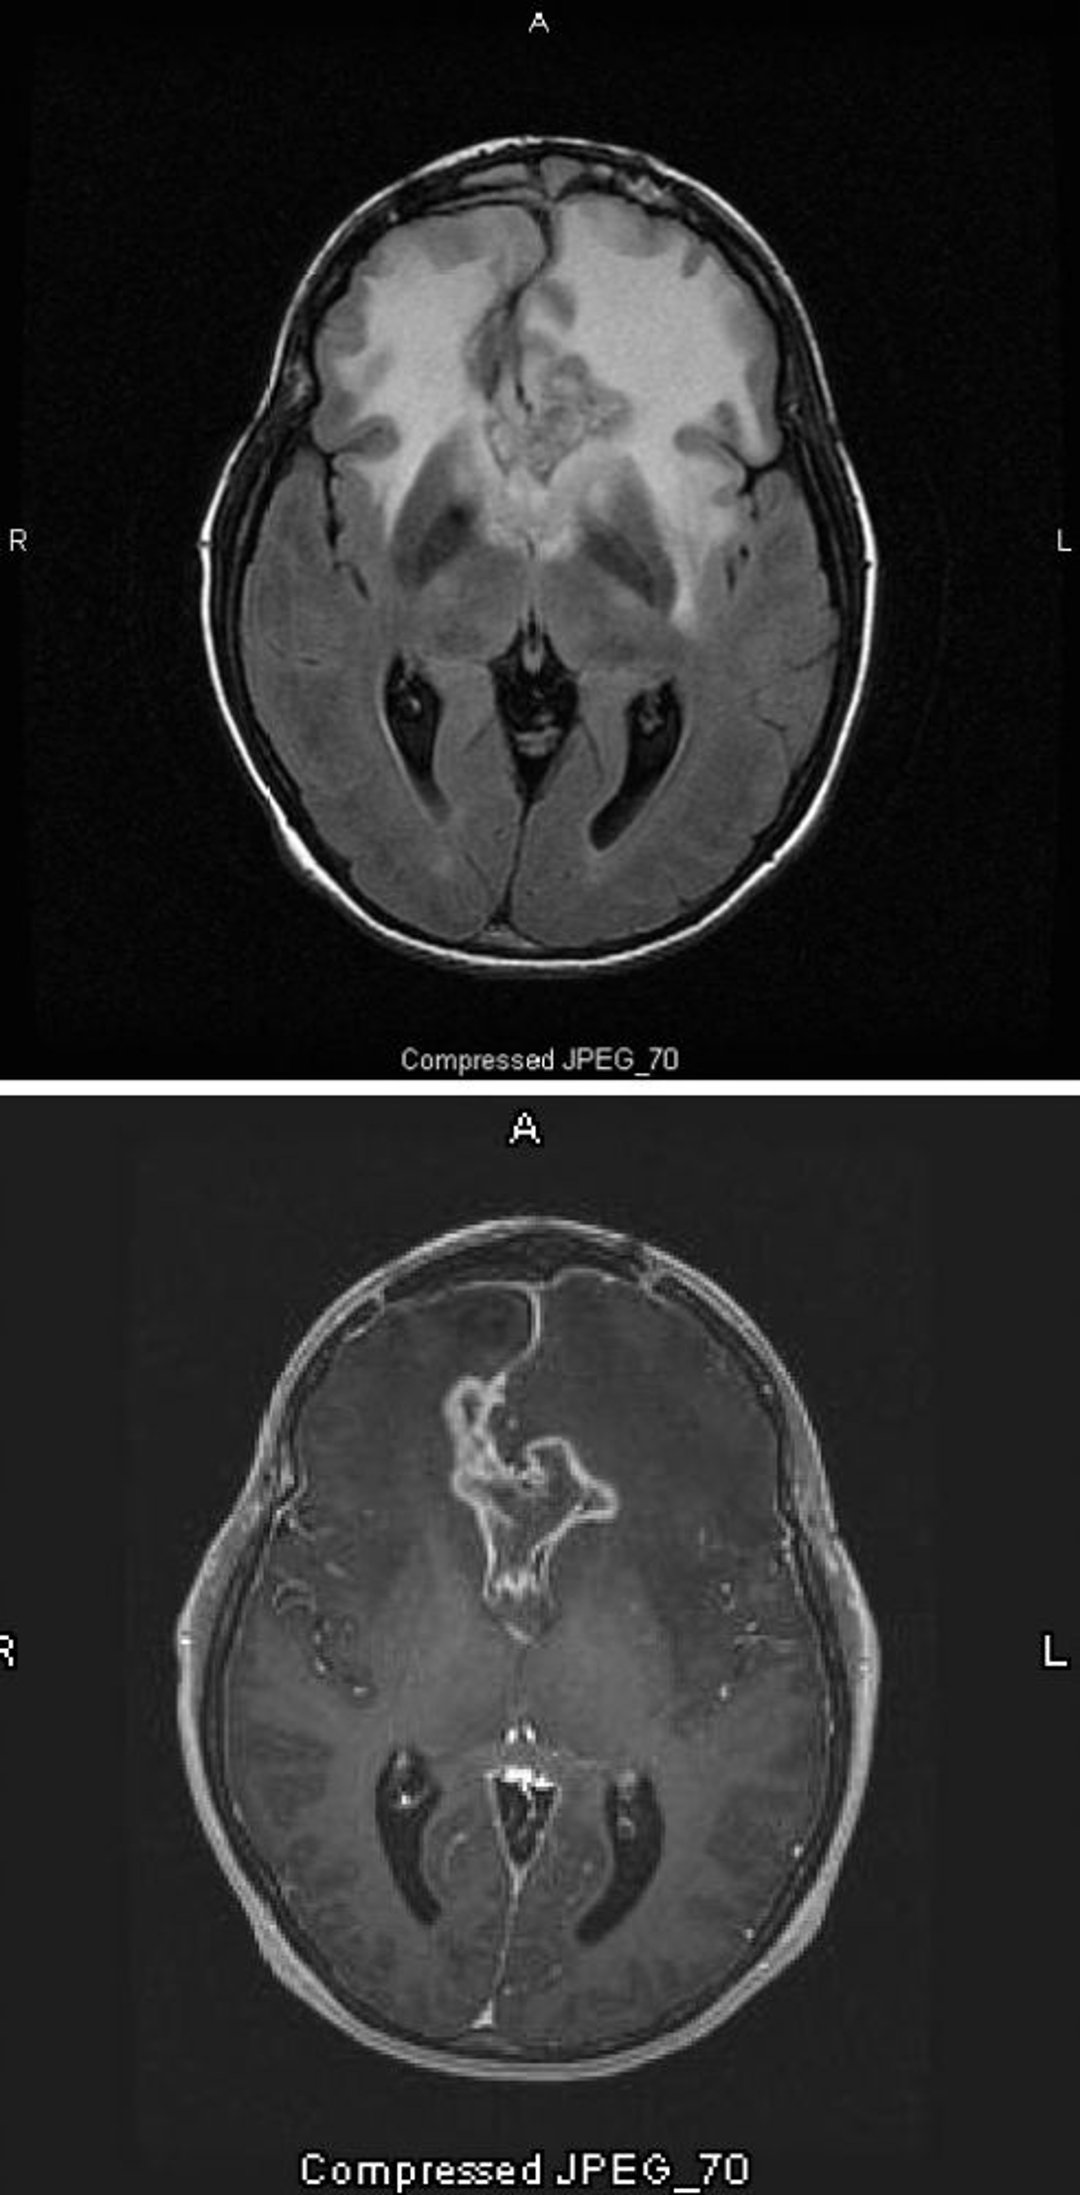

Глиобластома

Снимок T2-FLAIR МРТ (вверху) показывает большой двусторонний сигнал белого цвета (с повышенной плотностью) вокруг глиобластомы, которая является самой злокачественной и наиболее злокачественной астроцитомой. Эта специфическая глиобластома называется "глиомой бабочки", поскольку распространяется по полушариям, формируя крылья бабочки; это вызвано отеком мозга. На T1-взвешенном изображении (внизу) контраст очерчивает край опухоли (усиление окружности). Отек проявляется в виде затемненного участка (гипоинтенсивность) на T1.

Images courtesy of William R. Shapiro, MD.